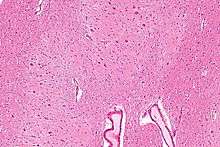

The dentate nucleus is a cluster of neurons, or nerve cells, in the central nervous system that has a dentate – tooth-like or serrated – edge. It located within the deep white matter of each cerebellar hemisphere, and it is the largest single structure linking the cerebellum to the rest of the brain.[1] It is the largest and most lateral, or farthest from the midline, of the four pairs of deep cerebellar nuclei, the others being the fastigial nucleus and the globose and emboliform nuclei which together are referred to as the interposed nucleus. The dentate nucleus is responsible for the planning, initiation and control of voluntary movements. The dorsal (towards the back of the body) region of the dentate nucleus contains output channels involved in motor function, which is the movement of skeletal muscle, while the ventral (towards the belly or front of the body) region contains output channels involved in nonmotor function, such as conscious thought and visuospatial function.

Morphology

The dentate nucleus is highly convoluted[3] and can be divided into dorsal (motor) and ventral (nonmotor) domains. The ventral half is much more developed in humans than in great apes, and it appears to play an important role in fiber connection. Further, the ventral domain mediates higher cerebellar functions, such as language and cognition, as well as versatile and coordinated finger movement.[8] While it is generally accepted that the ventral region is more recent on an evolutionary timescale, current 3-Dimensional imaging raises questions regarding this assumption, as a third axis, the rostrocaudal axis, can now be analyzed.[3] In addition, current images show that the ventral region is not physically larger than the dorsal region in humans, as would be predicted if size increases with cognitive function.[1]

The neurons of the adult dentate are divided based on size, morphology, and function into large principal and small local circuit neurons.[6]